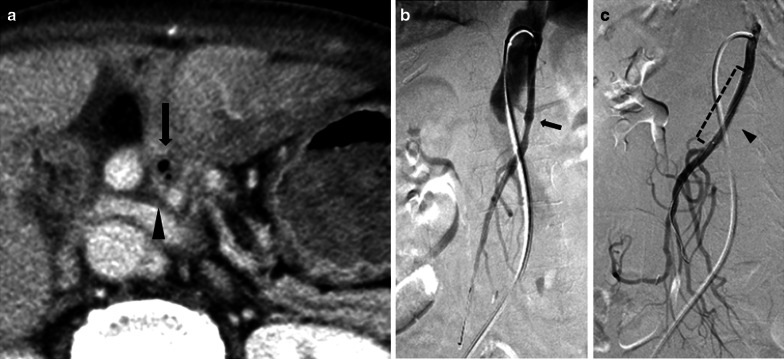

Fig. 3.

Evaluation using axial equilibrium phase contrast-enhanced computed tomography (CECT). a Axial equilibrium phase CECT shows the collection of gas (black arrow), an aneurysm of the superior mesenteric artery (black arrowhead) and the stomach filling with contrast fluid. b Superior mesenteric arteriography shows an aneurysm (black arrow), but extravasation was uncertain. c Arteriography after endovascular repair shows resolution of the aneurysm and preserved SMA blood flow through the covered stent (black arrowhead and dotted line)